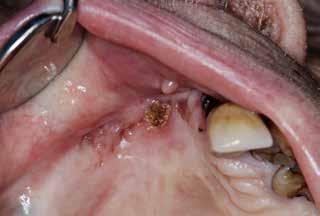

Den sidste artikel er en kasuistik, hvor en 72årig mand henvises fra egen tandlæge til Rigshospitalets kæbekirurgiske afdeling med en slimhindeforandring på margo gingivae, som blev angivet til at være fire uger gammel. Det viste sig at være et planocellulært karcinom. I Tandlægebladet 2023, nr. 10 omtaltes i en oversigtsartikel planocellulært karcinom. Denne maligne tilstand kan udvikle sig hurtigt, hvorfor det er vigtigt straks at henvise til et pakkeforløb i ørenæsehalsregi. For denne patient var karcinomet hurtigtvoksende, og det endte med, at patienten skulle behandles med stråleterapi. Et lærerigt tilfælde.♦

MADSEN M, LARSEN MK Oralt planocellulært karcinom / 598